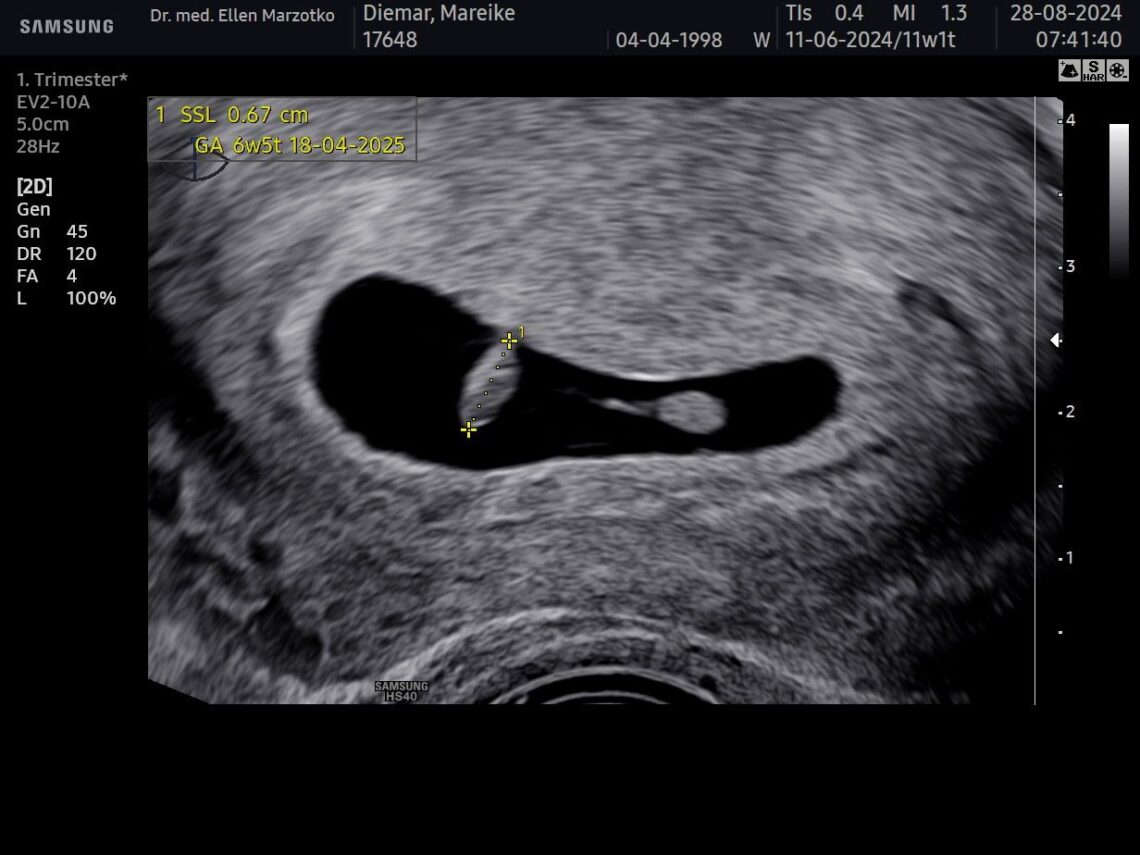

Wir haben dich zum ersten Mal gesehen 🥺

Am 28.08.2024 hatten wir unseren ersten Termin bei der Ärztin, die uns mitgeteilt hat, dass du da bist und dass…